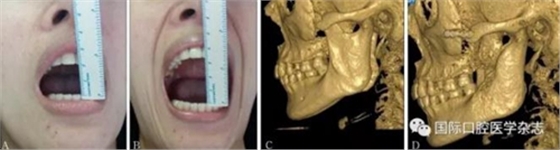

A:術前開口度;B:術后開口度;C:術前影像學檢查片;D:術后影像學檢查片。

圖 18 關節(jié)盤復位錨固術前后對比